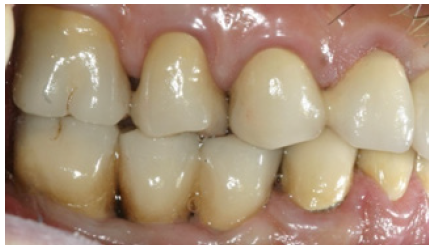

Figure 23: Right side view of final restorations (one year recall).

In order to optimize final aesthetics the 5 mandibular anteriors were prepared for all ceramic restorations. Four all ceramic veneers (E-max Ivoclar Co, Liechtenstein) and an all ceramic crown (#42) completed the final restorations. A final occlusal splint was also fabricated chairside (prior to the final cementation of ceramic veneers) for the protection of final restoration and control of TMJ function (Figure 19,20). Minimal occlusal modifications of the splint were necessary after final cementation of mandibular anteriors. The final radiographic examination was kept as a record for future re-examinations (Figure 21). Finally, the patient was enrolled to a 3 months recall program. In each recall and maintenance visit, the periodontal tissues, the abutments and the stomatognathic system were thoroughly examined, preventive regimens were applied and patient compliance was assessed. Two years later, the excellent periodontal condition and performance of the restoration was registrated (Figure 22-24). The patient complied with proper oral hygiene, reduced smoking and adopted a regular use of the occlusal splint. Strict recall and maintenance visits were necessary for long term success of this full mouth rehabilitation. The patient stopped smoking immediately after 6 months and changed nutritional habits in order to eliminate secondary caries.